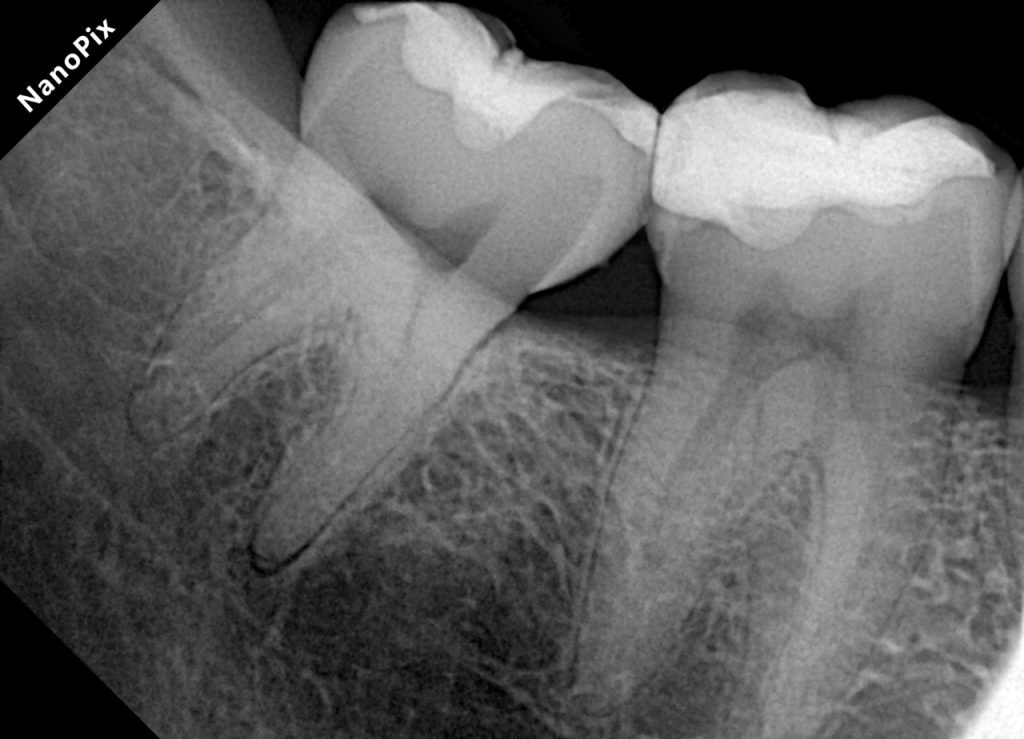

This case demonstrates the management of proximal caries in posterior teeth using direct composite restorations with proper isolation and sectional matrix technique. The goal was to achieve functional occlusion, tight proximal contacts, and seamless esthetics through minimally invasive adhesive dentistry.

1. Initial Presentation